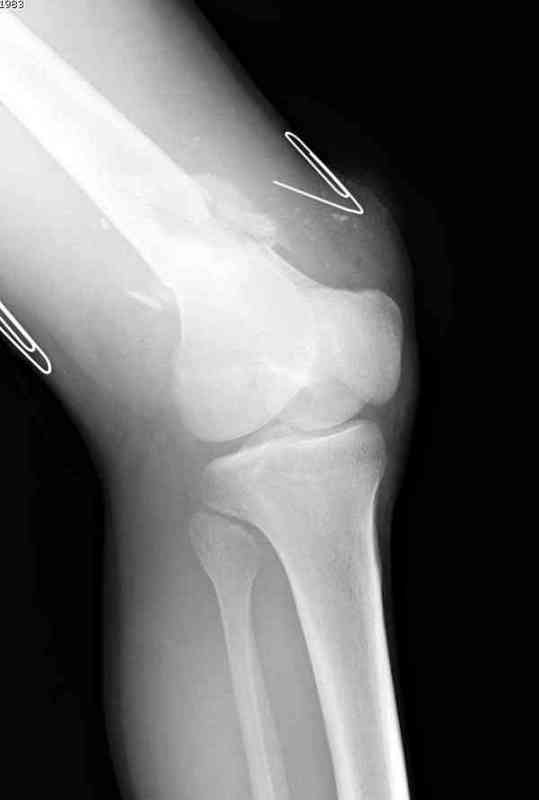

Больная К. с тугим ложным суставом н/3 бедра. Травма в 2005 г.-закрытый перелом, остеосинтез в аппарате Илизарова. В 2006 г. оперирована по поводу несросшегося перелома.

В ноябре 2006 г. демонтаж аппарата, после чего в течении месяца развилась вальгусная деформация. Имеется патологическая подвижность. Объем движений в коленном суставе 180-140. На обсуждение выносятся варианты лечения погружными конструкциями.

The patient with non-union of the distal femur. Trauma in 2005 - closed fracture of the femur, external fixation with Ilizarov apparatus. Non-union. In 2006 open reduction and external fixation with Ilizarov apparatus. In November 2006 the apparatus was removed, after that valgus deformation developed. There is pathological mobility. The knee motion 180-140. We'd like to discuss options of internal fixation.